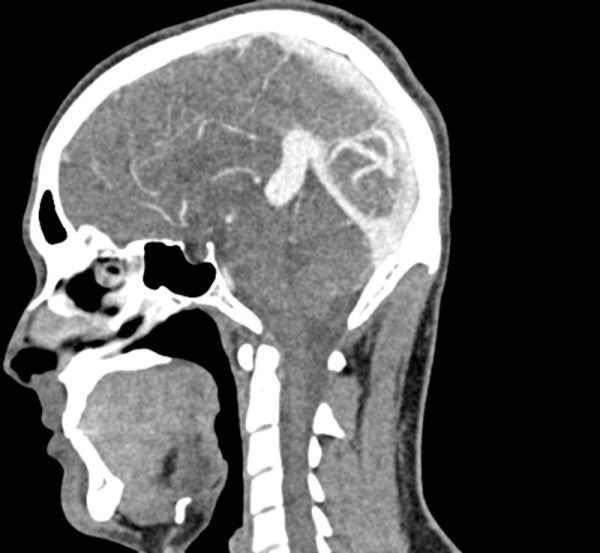

The Anatomy Phantom Models for CT, X-Ray, and Radiation Therapy offer healthcare students an authentic training experience with a non-contrast agent on a model. These anatomy phantom models accurately replicate tissue contrasts, providing a lifelike representation during imaging and radiation sessions.

The anatomy phantom models were created using state-of-the-art technology and are based on actual patient data, ensuring authenticity. They accurately display bones, vessels, and soft tissue with realistic values at 120 kVp tube voltage in CT scans. If used with different tube voltages, such as 100 kVp, the CT values can be adjusted for proper calibration.

The phantom models exhibit realistic tissue contrasts in X-ray imaging, and air spaces are filled with a material measuring approximately -80 Hounsfield units.